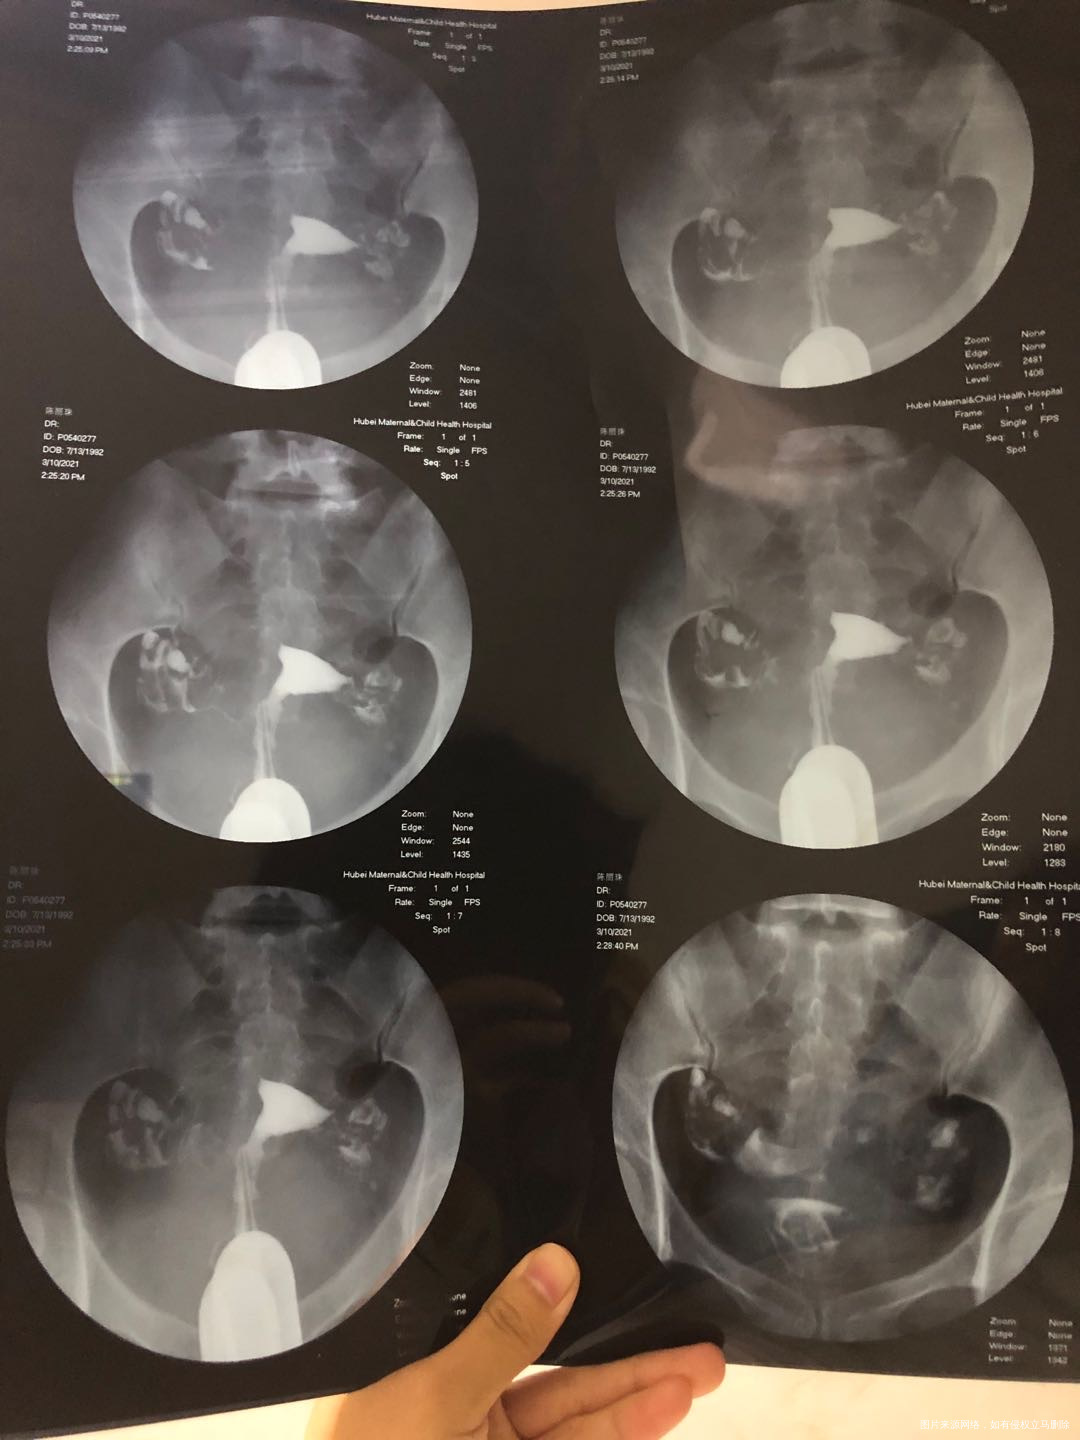

21年3月10日,例假干净后四天造影,结果双侧通而不畅,如图。